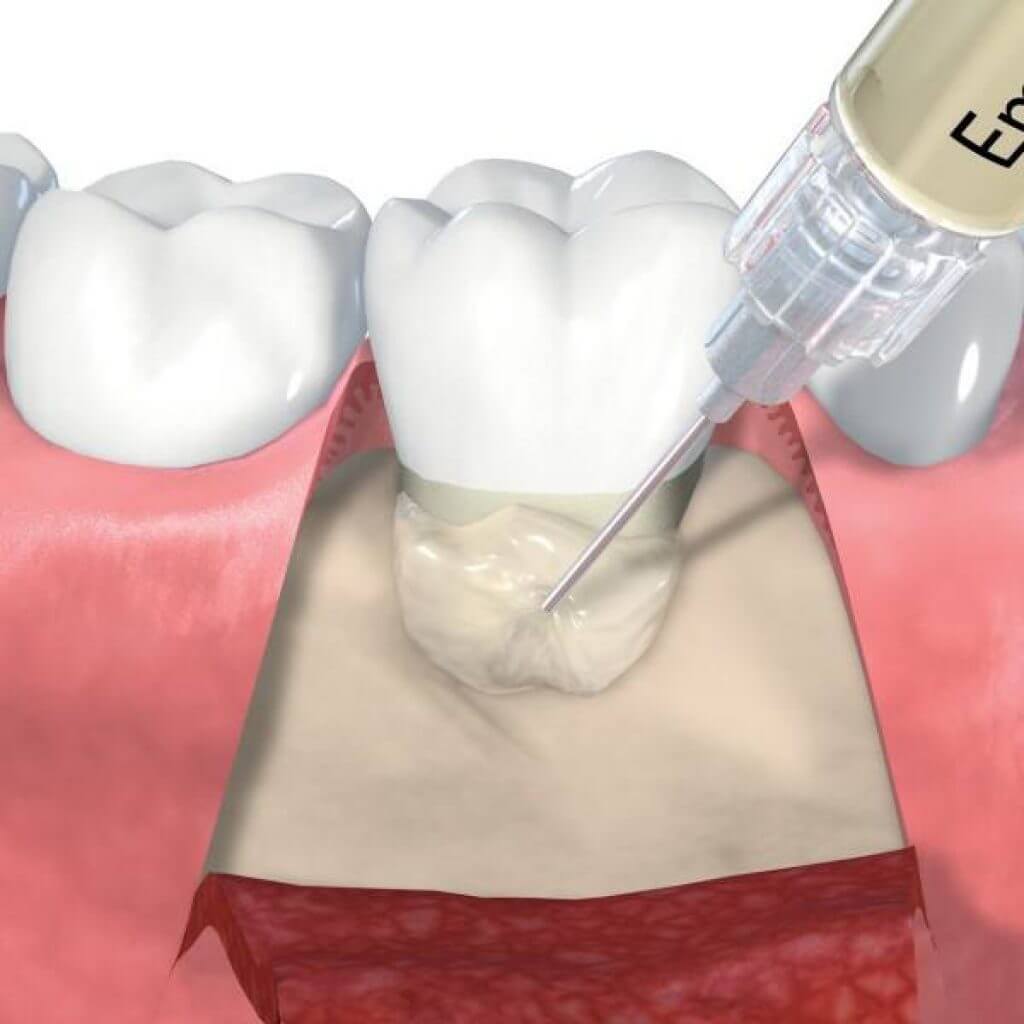

Фото и примеры имплантации зубов при пародонтите

Раздел: Необычные решения